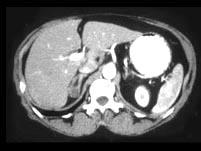

问题 女,35岁,无意中发现血压高,实验室检查:血和尿中醛固酮水平增高,请结合所提供图像,作出诊断 ( )

选项 A、右肾上腺转移瘤 B、右肾上腺囊肿 C、右肾上腺Cushing腺瘤 D、右肾上腺Conn腺瘤 E、右肾上腺增生

答案 D